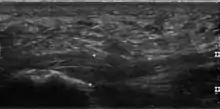

Medical imaging is not routinely needed. It is expensive and does not typically change how plantar fasciitis is managed.[15] When the diagnosis is not clinically apparent, lateral view X-rays of the ankle are the recommended imaging modality to assess for other causes of heel pain, such as stress fractures or bone spur development.[7]

The plantar fascia has three fascicles-the central fascicle being the thickest at 4 mm, the lateral fascicle at 2 mm, and the medial less than a millimeter thick.[19] In theory, plantar fasciitis becomes more likely as the plantar fascia's thickness at the calcaneal insertion increases. A thickness of more than 4.5 mm ultrasound and 4 mm on MRI are useful for diagnosis.[20] Other imaging findings, such as thickening of the plantar aponeurosis, are nonspecific and have limited usefulness in diagnosing plantar fasciitis.[13]